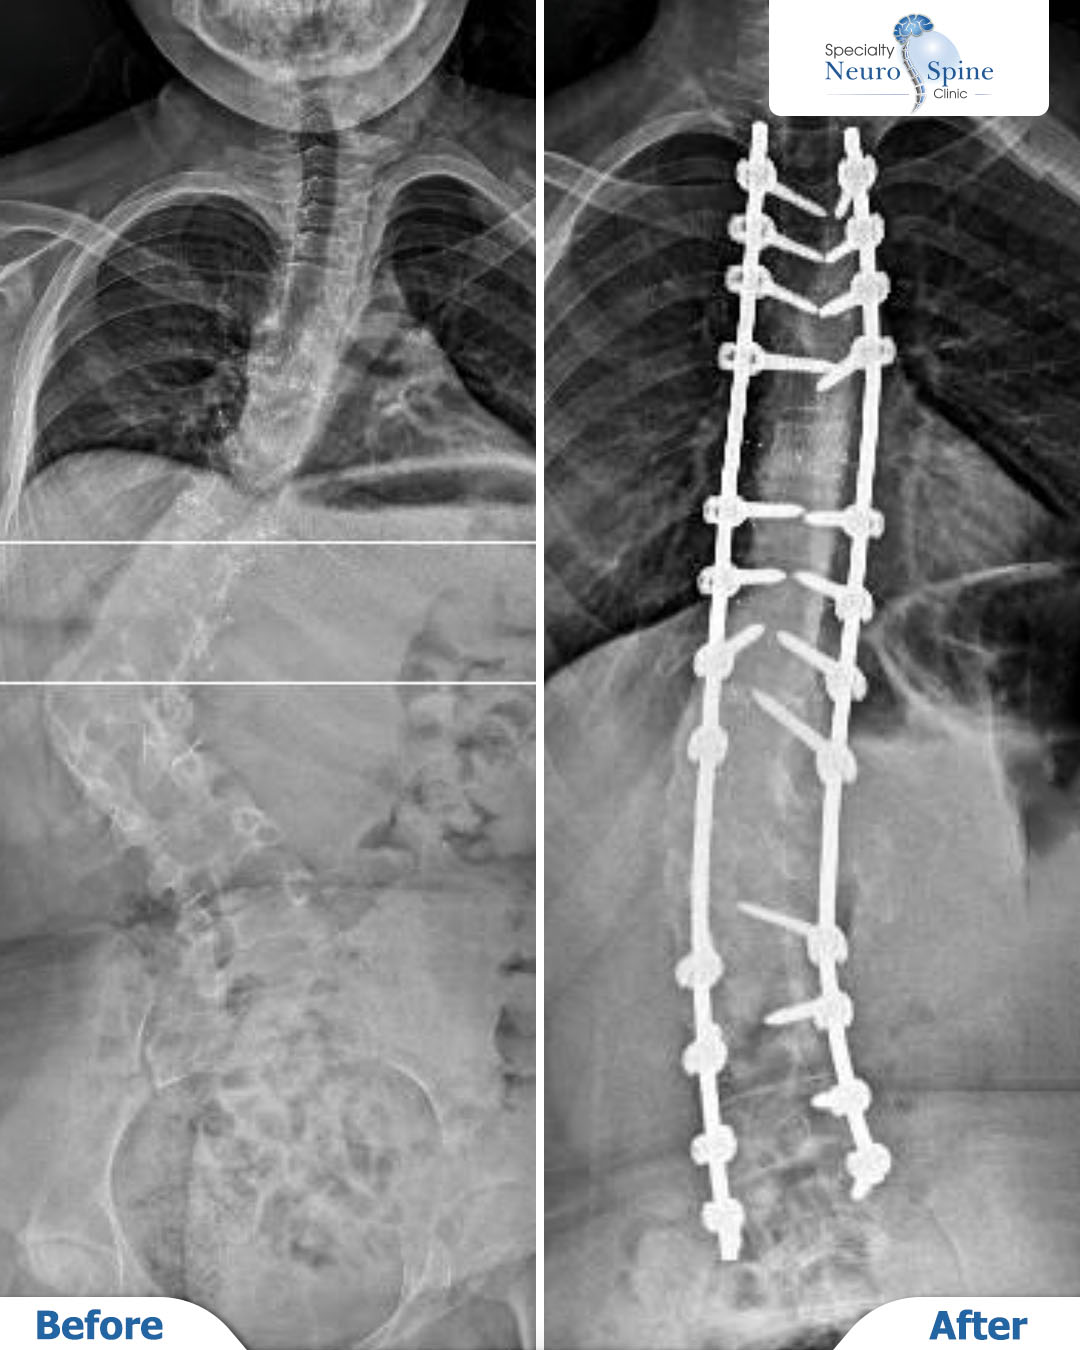

مريضتنا العزيزة زينب، 16 عامًا من البحرين، عانت من ورم في العمود الفقري وخضعت لعدة عمليات سابقة في ألمانيا لإزالته.

لكنها لم تُنصح حينها بإجراء عملية تصحيح الانحراف نظرًا لخطورتها.

بعد مراجعة حالتها بدقة من قبل الدكتور فراس الحُسبان، طمأن العائلة وأكد إمكانية إجراء العملية بأمان بفضل التقنيات الحديثة المتوفرة لديه.

اليوم، وبعد نجاح العملية، نشارككم هذه اللحظة التي تعكس استقامة العمود الفقري واستقرار الحالة.